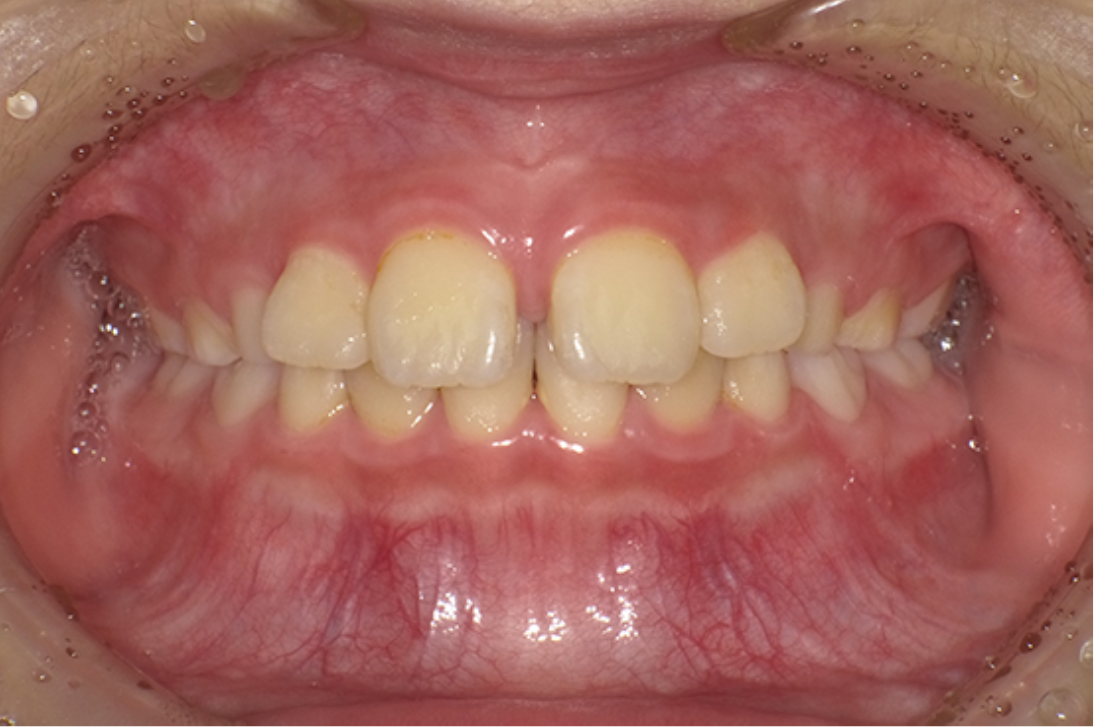

• 治療前

• 治療後

主訴:前歯のすき間が気になる診断:正中離開

治療内容:小児矯正治療

年齢:9歳

治療に用いた装置:機能的矯正装置

抜歯or非抜歯:非抜歯

期間:24ヶ月

回数:15回

費用:467,500円(税込)

リスク・副作用:虫歯、歯肉炎、歯肉退縮、歯根吸収、後戻りなど